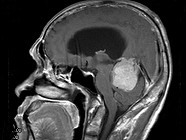

- 单项选择题男,61岁, 头晕头痛伴行走不稳1月余,请根据所提供图像, 诊断最有可能是 ( )

A、转移瘤

B、胶质瘤

C、淋巴瘤

D、髓母细胞瘤

E、(天幕切迹缘)脑膜瘤